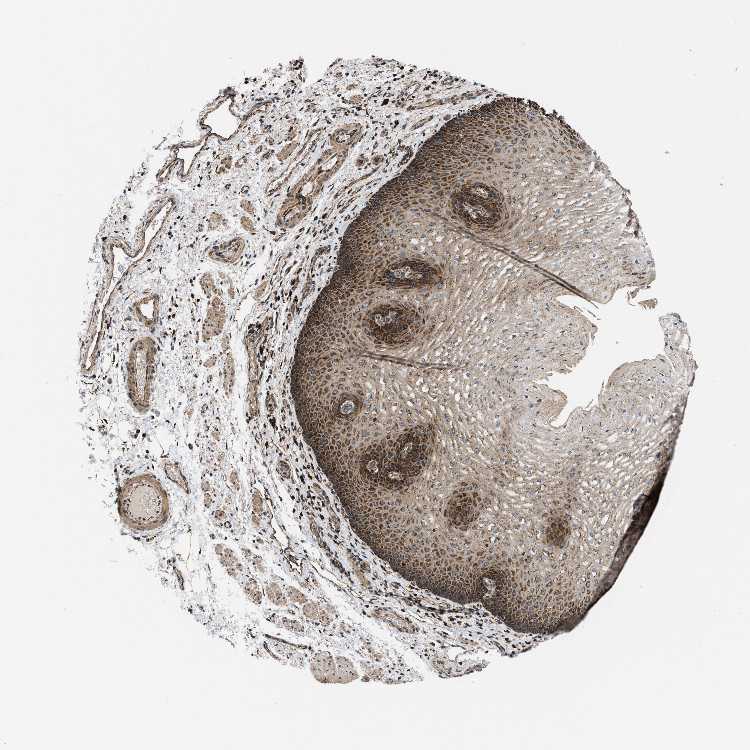

ESOPHAGUS - Antibody stainingi

Antibody staining in the annotated cell types in the current human tissue is reported as not detected, low, medium, or high, based on conventional immunohistochemistry profiling in selected tissues. This score is based on the combination of the staining intensity and fraction of stained cells.

Each image is clickable and will lead to virtual microscopy that enables deeper exploration of all samples and also displays staining intensity scores, fraction scores and subcellular localization as well as patient and tissue information for each sample.

Antibody HPA003279Antibody HPA003360Antibody CAB019303

Squamous epithelial cells Not detectedMediumHigh